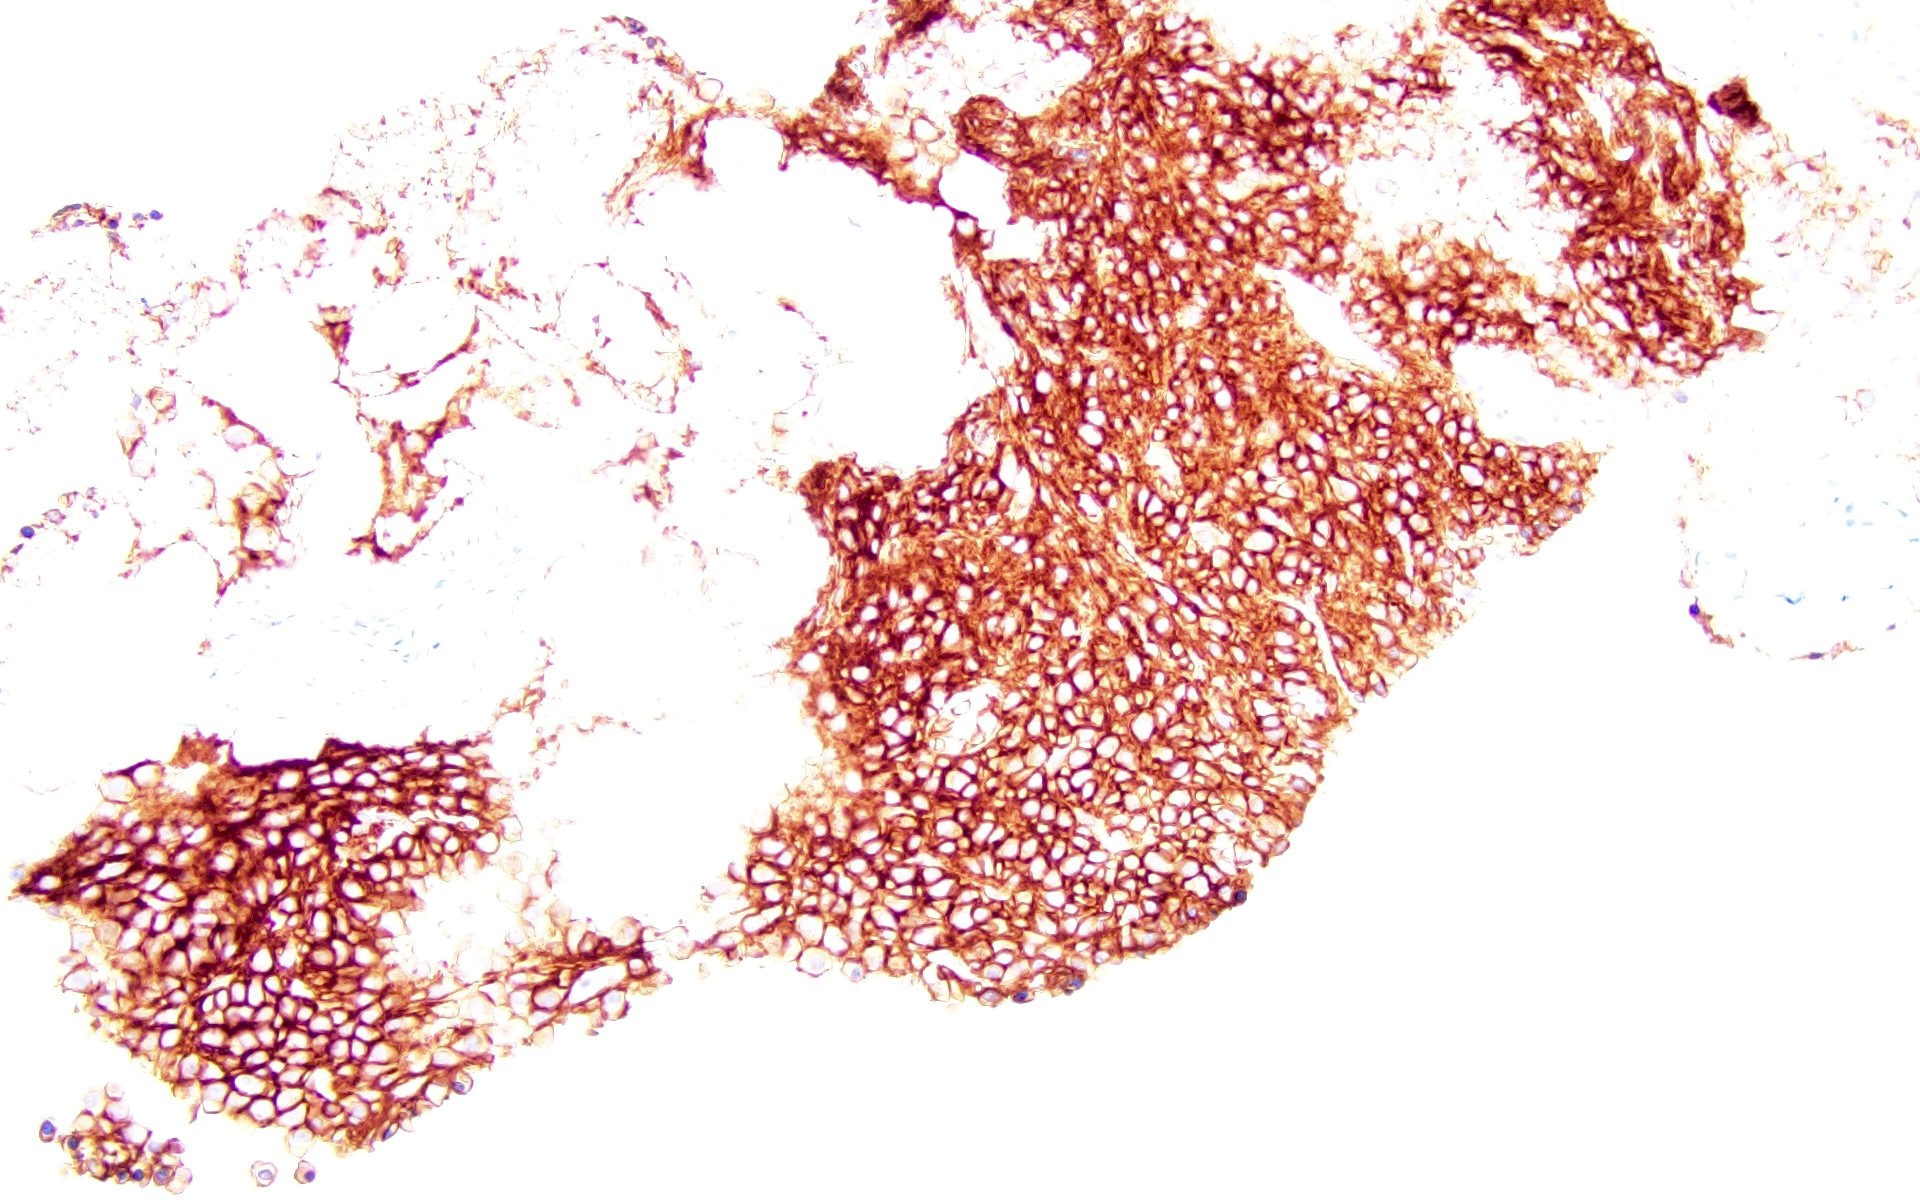

Positive stains

- CD38, CD138, MUM1, CD229, CD48, CD272, CD319 (Cytometry B Clin Cytom 2016;90:91, Cytometry B Clin Cytom 2019;96:338, Cytometry B Clin Cytom 2016;90:81)

- Either kappa or lambda cytoplasmic immunoglobulin light chain expression

- Positive for CD138, CD38, restricted cytoplasmic light chain and negative for CD19

- Flow cytometric analysis revealed a cytoplasmic lambda light chain restricted monotypic plasma cell population (~23% of total CD45+ leukocytes) that is CD138+, CD38+, CD19-, CD20-, CD81-, partial CD27+, CD56- and CD117-. A polytypic B cell population is identified.

- Comment: The biopsy shows sheets of small plasma cells which are lambda restricted based on kappa / lambda in situ hybridization studies. EBER ISH is negative. Ki67 shows low proliferative index (< 5%). Clinical correlation with serology, imaging and bone marrow biopsy is suggested.